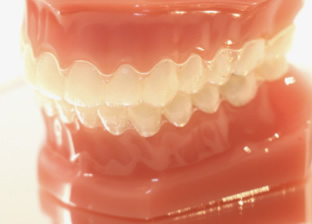

カスタムメイド型マウスピース矯正

インビザライン

インビザラインとはどんなもの?

インビザラインはアメリカのアラインテクノロジー社が開発したマウスピース型の矯正装置です。これまでに全世界で700万人(2019年6月現在)を超える患者様が治療を受けられており、その数は年々増加しています。今までのワイヤー矯正では難しかった、取り外しができ、見た目が良いなどメリットは多くあります。また痛みも少ないとも言われています。

その人気はアラインテクノロジー社の株価がうなぎ登りなのを見てもわかると思います。あなたの生活スタイルにあった賢い大人の選択、インビザラインを選択されてみてはいかがですか?